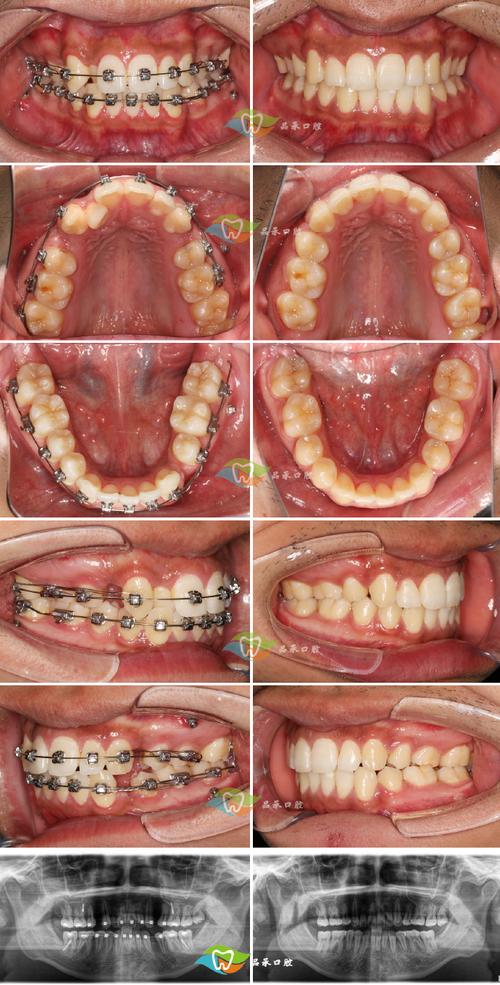

两者在临床中常联合分析:高角病例常伴IMPA增大(下前牙代偿性唇倾以维持切牙功能),需警惕治疗中垂直向失控;低角病例多见IMPA减小(下前牙舌倾以适应深覆颌),治疗中需避免前牙过度舌倾加重深覆颌,对高角开颌患者,正畸治疗需通过压低后牙、控制下颌平面旋转来减小FMA,同时内收下前牙减小IMPA,以稳定咬合与面型;对低角深覆颌患者,则可能需升高后牙打开咬合,唇倾下前牙增加IMPA,改善覆颌关系。

A:需根据垂直向与矢状向问题综合设计,高角(FMA>30°)患者,优先控制垂直向:使用摇椅弓、微种植体压低后牙,减小下颌平面旋转,同时通过内收下前牙(如滑动法关闭拔牙间隙)减小IMPA,避免前牙过度唇倾,低角(FMA<20°)患者,需增加垂直高度:可采用平面导板、J钩高位牵引打开咬合,同时唇倾下前牙(片段弓或下颌弓丝弯制“Spee”曲线)增加IMPA,改善深覆颌,若IMPA单独异常(如过大导致露龈笑),可通过多曲唇弓、种植支抗内收下前牙;过小时需去除干扰、唇倾前牙,但需注意牙周健康,避免牙根吸收。